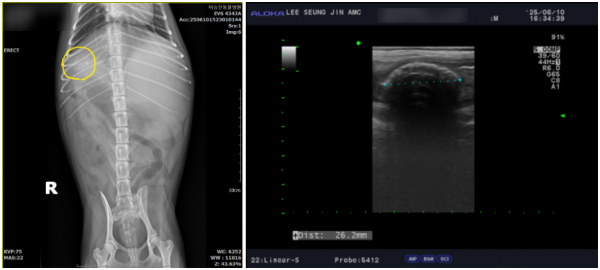

그 결과, 하늘이의 오름십이지장 속 에 씨앗 형태의 이물이 확인되었으며

이로 인해 심한 장염, 복막염, 췌장염이 동반되어 있었습니다.

즉시 내원하여 영상검사(엑스레이·초음파) 및 종합적인 검사를 통해